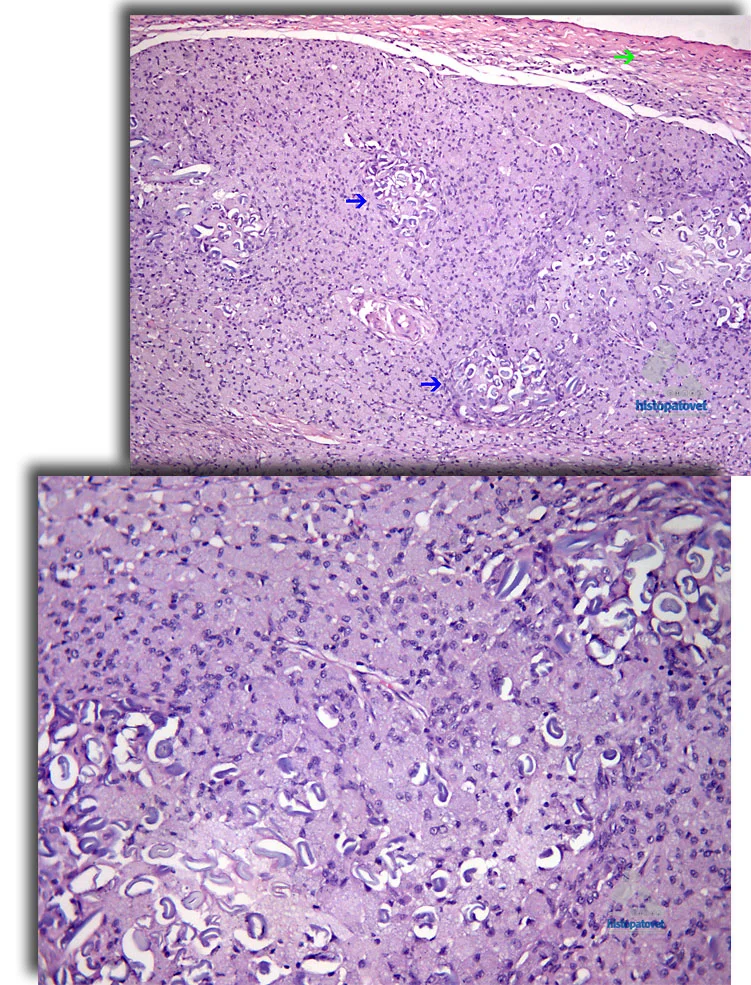

Microscópicos: hay una cápsula gruesa, la cual externamente está compuesta por un tejido adiposo y fibroso. Más internamente, hay múltiples centros de un material un poco gris, seccionado longitudinal y transversalmente, el cual dio positivo a la luz polarizada. Este material está a su vez rodeado por muchos histiocitos con un citoplasma espumoso; aún mas internamente hay un tejido necrótico y amarillento. Ver las siguientes figuras.

Fig.3 A-B. La flecha verde señala la cápsula de la masa. Las azules indican centros de un material extraño. Abajo hay un mayor detalle, observe que hay muchos macrófagos (citoplasma espumoso) rodeando al material.

Fig. 4 A-B. Observe que en algunos centros hay un pigmento amarillento( quizás tipo ceroide), el cual está en contacto con el material extraño. En la foto superior, el logo de histopatovet, esta ubicado en una zona de mucha necrosis. La foto inferior para un mayor detalle.